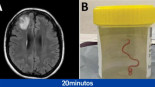

Extraen un gusano vivo de 8 centímetros del cerebro de una mujer

Un gusano de 8 centímetros de largo ha sido extraído vivo del cerebro de una mujer en Australia, en una cirugía del lóbulo frontal. El gusano, una larva de la especie Ophidascaris robertsi, es un parásito que suele invadir los cuerpos de diferentes especies animales, pero esta ha sido la primera vez que han encontrado al anélido en un ser humano.